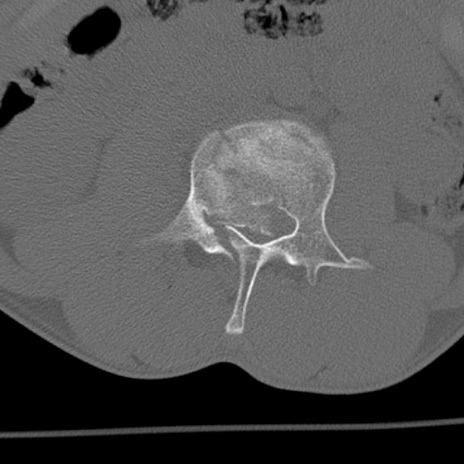

症例3 腰椎CT(横断像)

腰椎CT